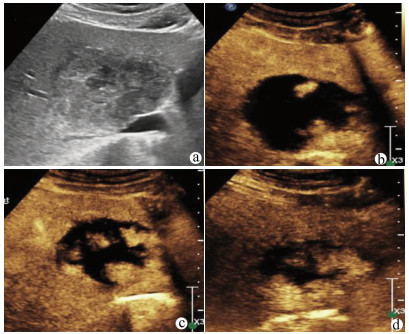

Guideline for ultrasonic diagnosis of liver diseases

Chinese Society of Ultrasound in Medicine, Oncology Intervention Committee of Chinese Research Hospital Society, National Health Commission Capacity Building and Continuing Education Expert Committee on Ultrasonic Diagnosis

2021, 37(8): 1770-1785. DOI: 10.3969/j.issn.1001-5256.2021.08.007

Abstract(3025) HTML (6526) PDF (9311KB)(794)

Abstract:

Ultrasound is a non-invasive, real-time, inexpensive, radiation-free and easily repeatable method, usually used for liver imaging. In recent years, new ultrasound examination techniques for liver diseases such as contrast-enhanced ultrasound and elastography have been rapidly developed, which can effectively identify intrahepatic space-occupying lesions, assess the degree of liver fibrosis and portal hypertension, and monitor the effects of treatment. Therefore, these technologies play an important diagnostic role in clinical liver diseases and have therapeutic interventional value. This guideline classifies the instrument set-up, patient preparation, and physician examination methods through multimodal ultrasound examinations (gray-scale ultrasound, color Doppler ultrasound, contrast-enhanced ultrasound, elastic ultrasound) for liver diseases. In addition, liver diseases multimodal ultrasound technology diagnostic criteria for diffuse hepatic lesions (inflammatory lesions, fibrosis, and sclerosis), multiple space-occupying lesions, and interventional procedures have been defined and standardized. Concurrently, we also recommend the ultrasound monitoring time interval and diagnostic report writing standard for liver diseases.